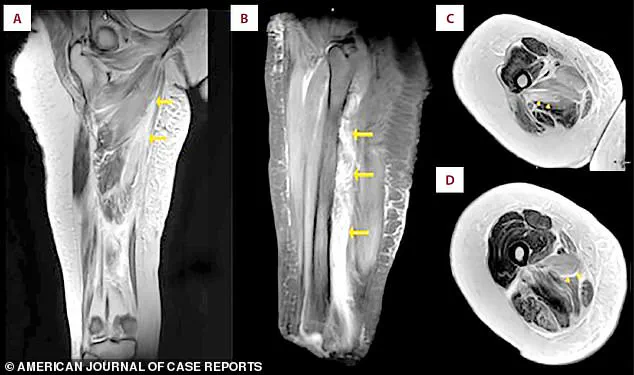

An MRI scan of the patient's right thigh revealed widespread muscle swelling.

The images, marked with arrows, pinpointed this fluid buildup in the inner thigh muscles (the adductor group) and, in a different view, showed similar swelling affecting the muscles at the back of the thigh.

The MRI provided a detailed anatomical map of the damage, revealing the extent of the swelling and the specific muscle groups affected.

The fluid accumulation was a clear indicator of the inflammatory response and the breakdown of muscle tissue, offering valuable insights into the patient's condition and guiding further treatment decisions.